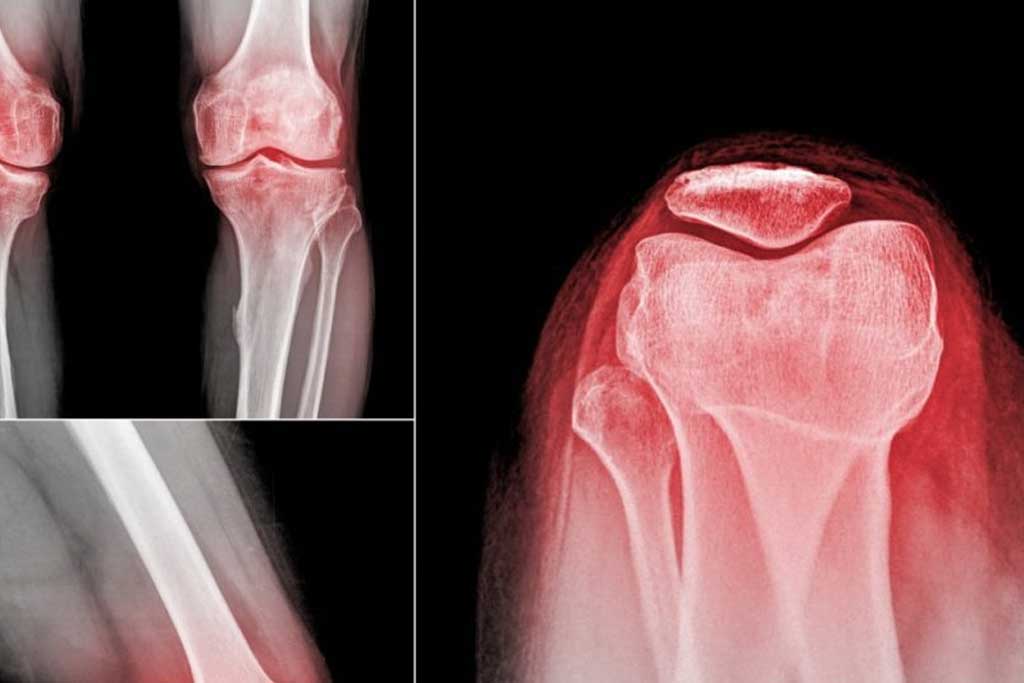

رادیوگرافی تری جوینت، تصویربرداری از سه مفصل کلیدی اندام تحتانی شامل ران، زانو و مچ پا است. هدف این تصویربرداری، بررسی همراستایی اندام تحتانی در حالت ایستاده و تعیین میزان تغییر شکل یا انحراف مفاصل است.

این روش معمولاً برای بیماران نیازمند جراحی تعویض زانو، اصلاح تغییر شکلهای اندام، ارزیابی آرتروز پیشرفته یا تحلیل محور مکانیکی بدن انجام میشود. برخلاف رادیوگرافی معمولی یک مفصل، رادیوگرافی تری جوینت تمام اندام از ران تا مچ پا را پوشش میدهد و تصویری یکپارچه ایجاد میکند.

۳. ارزیابی آرتروز و تغییرات دژنراتیو

رادیوگرافی تری جوینت امکان بررسی کجی و انحراف مفاصل ناشی از آرتروز را فراهم میکند. پزشکان با بررسی زاویهها و محور مکانیکی، شدت آسیب و میزان تغییر شکل را تعیین کرده و برنامه درمانی بهینه ارائه میدهند.